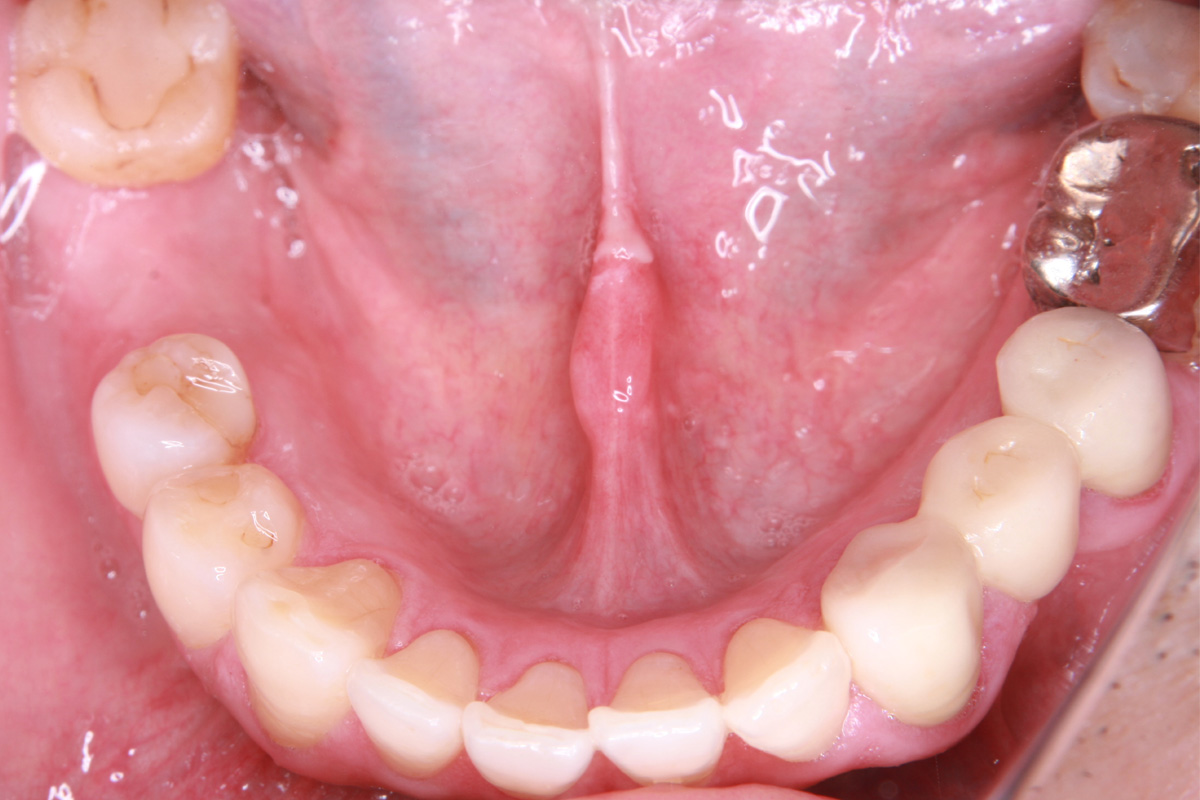

抜歯した箇所にインプラント治療を行った例

術前・術後の比較

初診時

歯が割れていて、痛みがあり、抜歯となりました。

親抜歯後、歯ぐきは治癒しました。しかし、インプラント治療のためには骨が不足していました。

骨移植(人工骨+メッシュプレート)を行い、骨を造りました。

インプラント手術を行いました。

レントゲン画像 治療前 インプラント治療後